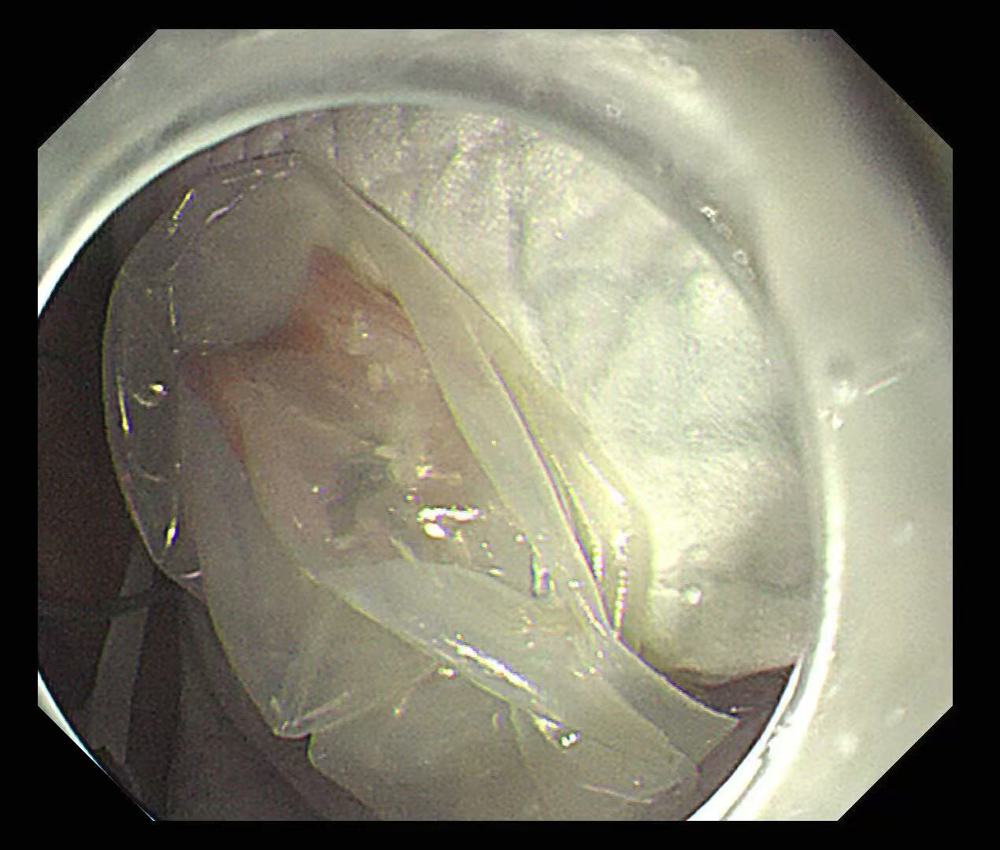

她先将假牙小心地套入特制的医用灭菌隔离透明膜中,如同为其穿上了一层光滑的“保护衣”。这一关键步骤,能有效包裹住假牙的尖锐钩环,极大降低了拖拽过程中对消化道黏膜的划伤风险。

在团队紧密协作下,被妥善包裹的假牙随着胃镜被平稳、缓慢地经食管取出体外。整个手术过程顺利,张奶奶的消化道黏膜完好无损,成功避免了可能的内镜创伤。术后,张奶奶恢复良好,她对医护团队的精湛技术与暖心照护感激不已。